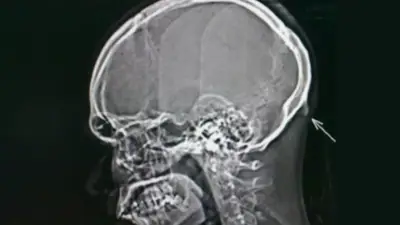

Un equipo de investigadores de la Universidad de Sunshine Coast, en Australia, cree que la aparición de una protuberancia en la base del cráneo, se debe al uso intensivo del móvil y estaría destinada a ayudar a repartir el peso de la cabeza, siempre inclinada.

Conocido como protuberancia occipital externa, el nuevo bulto óseo puede llegar a ser tan grande que es posible sentirlo al presionar con los dedos.

Aunque aún no se ha identificado una relación de causa-efecto, Shahar cree que ese nuevo refuerzo óseo tiene que ver con el hecho de estar doblando continuamente el cuello en incómodos ángulos para mirar las pantallas de los móviles. La cabeza humana es muy pesada (4,5 kilogramos como promedio) y al inclinarla continuamente hacia delante para leer mensajes en WhatsApp o ver vídeos divertidos, estamos obligando al cuello a soportar todo ese peso durante mucho más tiempo de lo que sería natural.